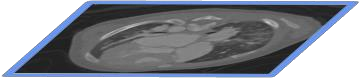

The success of deep learning heavily depends on the availability of large labeled training sets. However, it is hard to get large labeled datasets in medical image domain because of the strict privacy concern and costly labeling efforts. Contrastive learning, an unsupervised learning technique, has been proved powerful in learning image-level representations from unlabeled data. The learned encoder can then be transferred or fine-tuned to improve the performance of downstream tasks with limited labels. A critical step in contrastive learning is the generation of contrastive data pairs, which is relatively simple for natural image classification but quite challenging for medical image segmentation due to the existence of the same tissue or organ across the dataset. As a result, when applied to medical image segmentation, most state-of-the-art contrastive learning frameworks inevitably introduce a lot of false-negative pairs and result in degraded segmentation quality. To address this issue, we propose a novel positional contrastive learning (PCL) framework to generate contrastive data pairs by leveraging the position information in volumetric medical images. Experimental results on CT and MRI datasets demonstrate that the proposed PCL method can substantially improve the segmentation performance compared to existing methods in both semi-supervised setting and transfer learning setting.